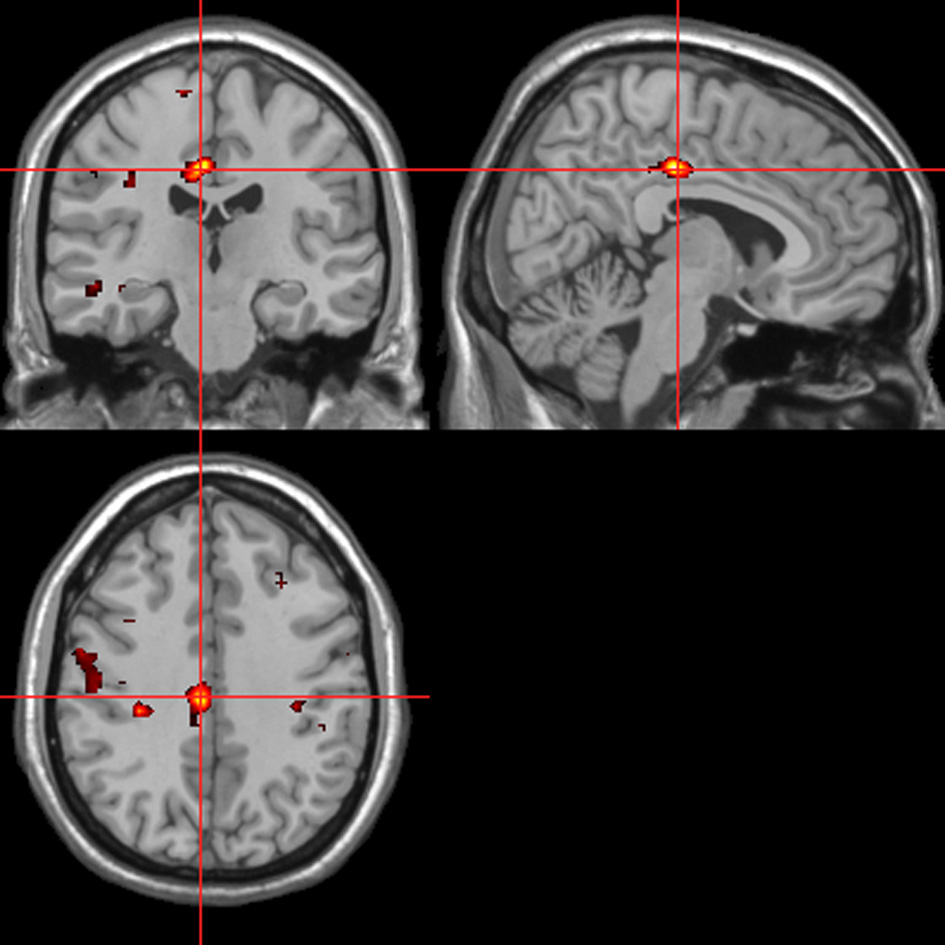

fMRI—autonomic (ISCR) regressor

Across all stimuli (i.e., without differentiating between modalities), ISCR was associated with activations including bilateral precentral gyrus/supplementary motor area [SMA; Brodmann's Area (BA) 4/6], medial prefrontal cortex (mPFC; BA 8), precuneus/cuneus (BA 7/19), thalamus [dorso-medial (DM) nucleus], bilateral lingual gyrus (BA 18) and cerebellum (Table 1; Figure 5; p < 0.05 FWE). Separately, for picture, sentence and sound stimuli, this dorsal (precentral gyrus/SMA) and posterior (lingual gyrus/cerebellum) activation was replicated, though the DM-thalamic activation was only present for picture and sentence stimuli (i.e., not sounds). However, sound-stimuli ISCR data were associated with activation of left amygdala.

Picture, sentence, and sound stimuli. Brain activations associated with integrated skin conductance response (ISCR) activity (see Figure 5).

Co-ordinates are shown in standardized neuroanatomical space (Talairach and Tournoux, 1988). R, right; L, left; BA, Brodmann's area; SMA, supplementary motor area; mPFC, medial prefrontal cortex; MidFG, middle frontal gyrus; DM, dorso-medial. Co-ordinates without a corresponding extent threshold are shown in italics and refer to sub-clusters of the preceding activation. P < 0.05 corrected for family wise error (FWE).

Figure 5

ISCR regressor across picture, sentence, and sound stimuli. Main effect of autonomic arousal. Flexible factorial design. p < 0.05 corrected for family-wise error (FWE). Extent threshold = 10. See Table 1 for anatomical descriptions and co-ordinates.